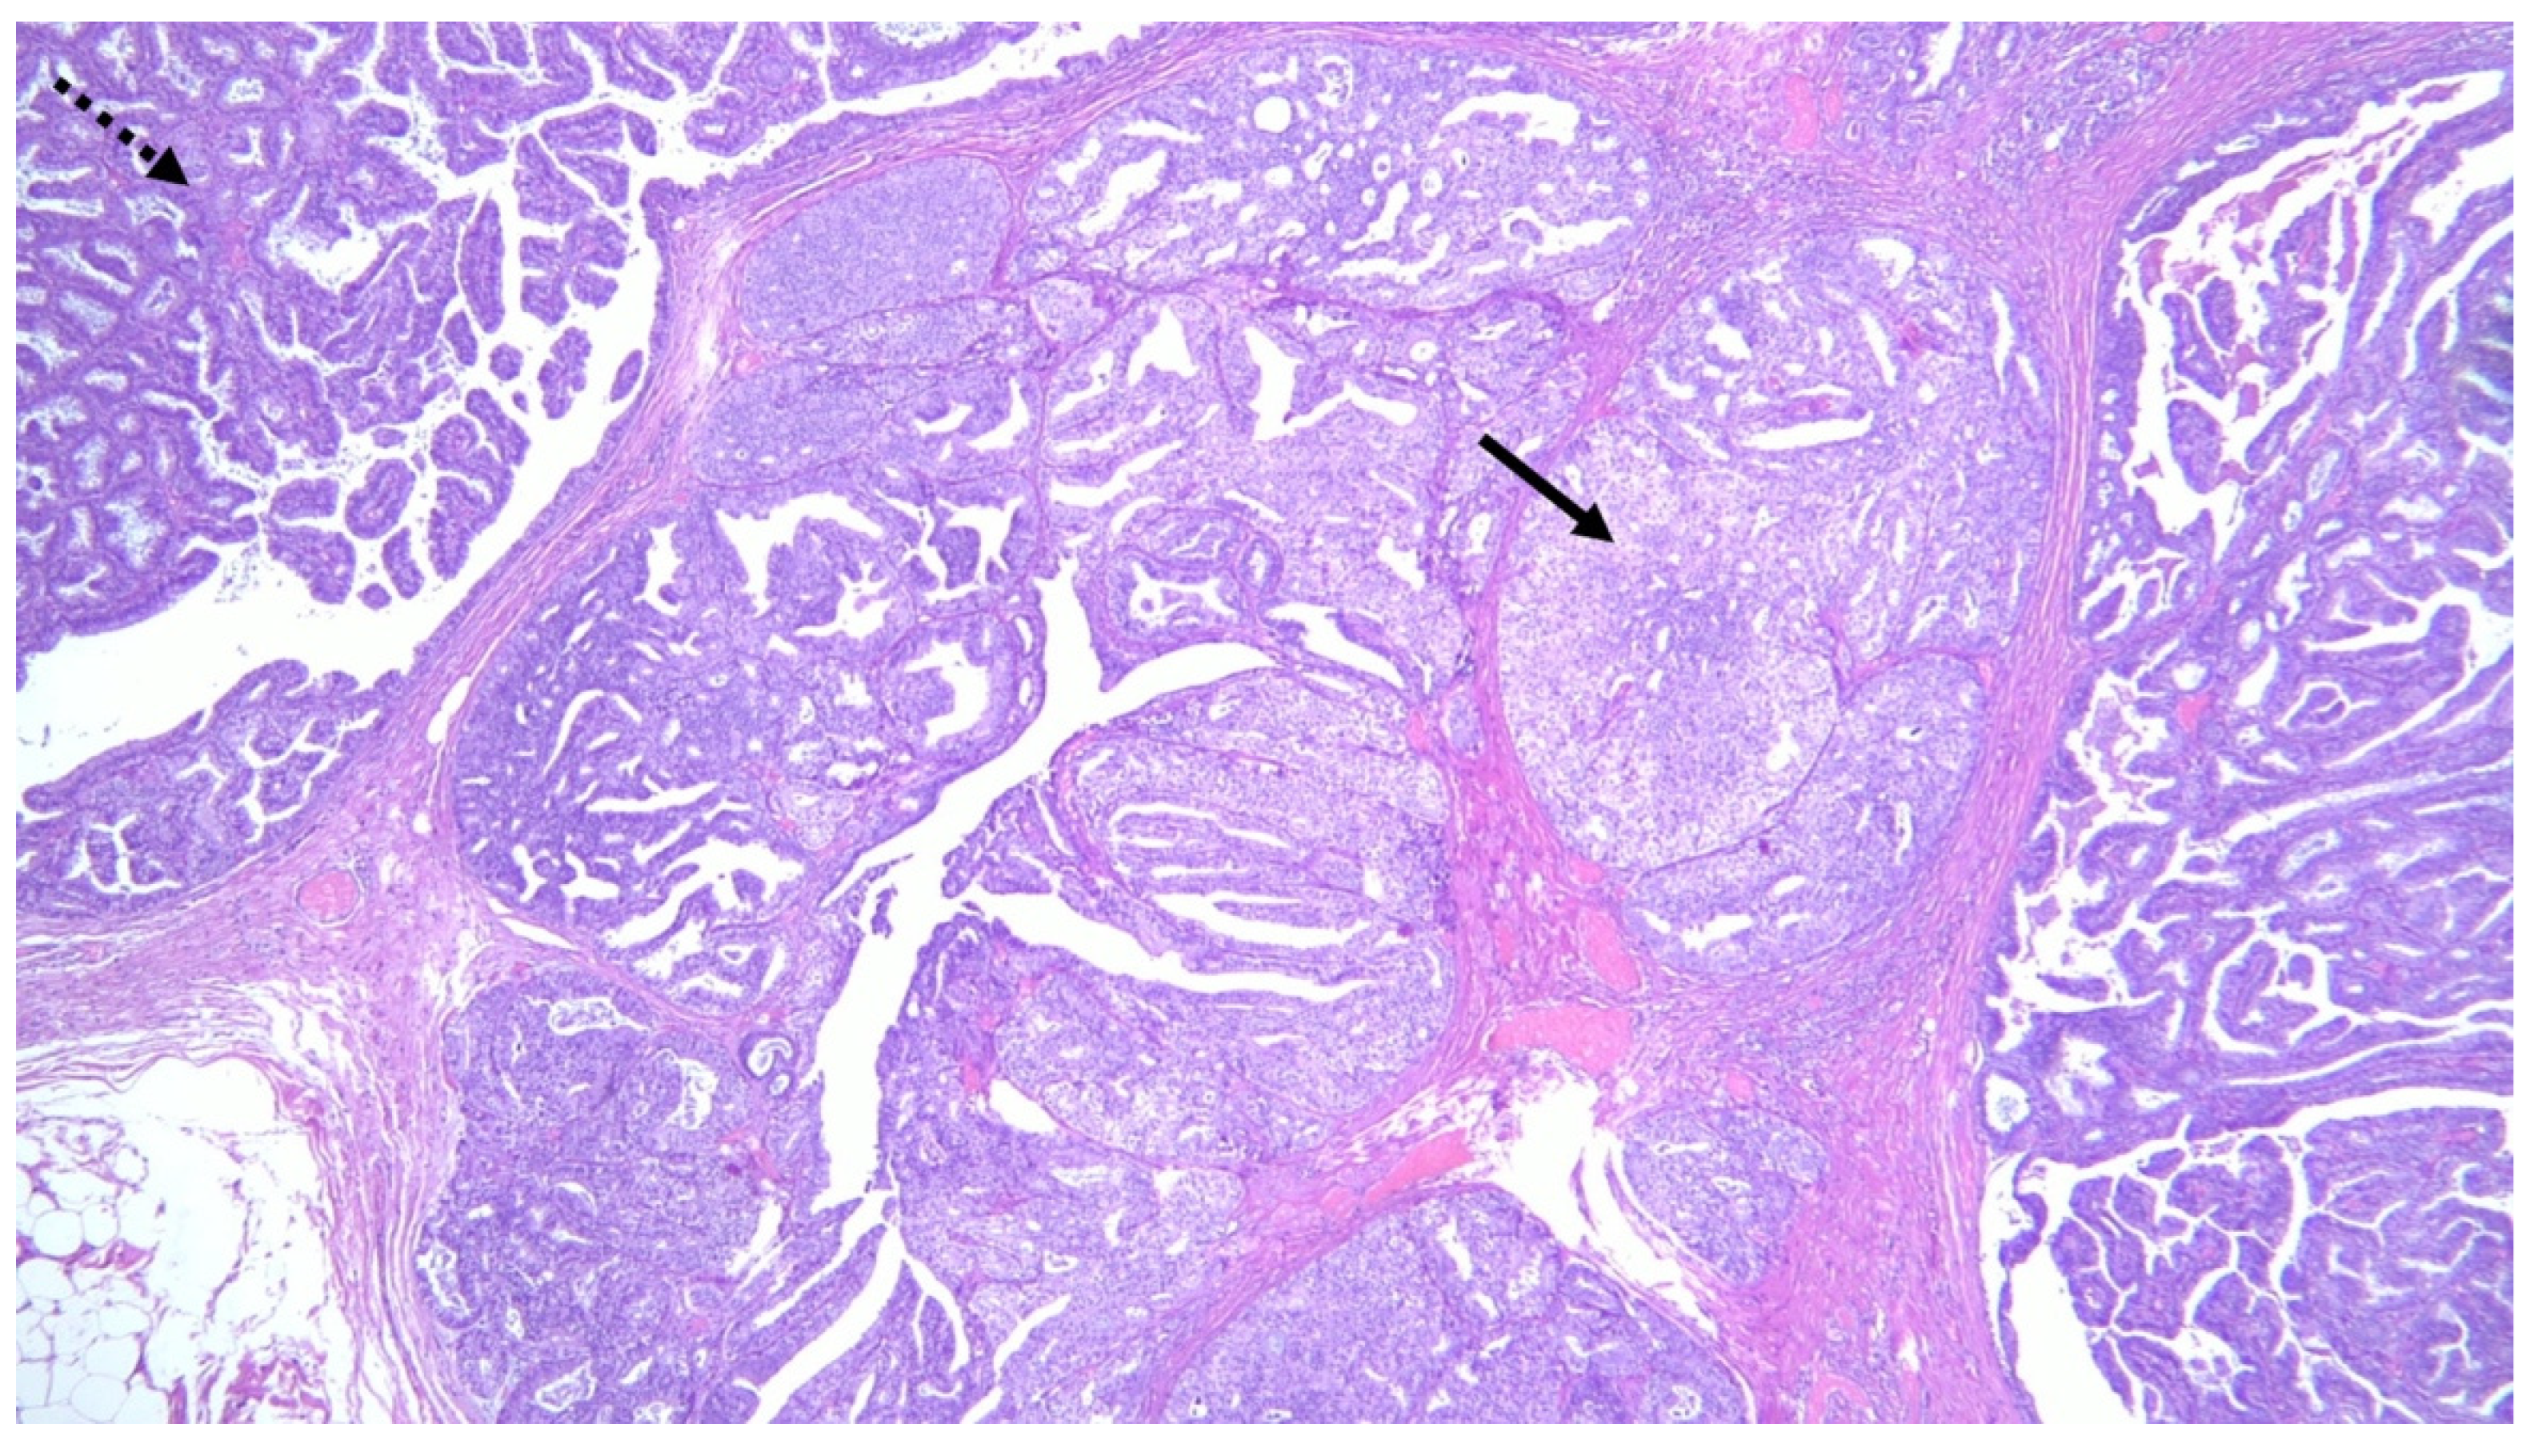

3.2. MP and Malignancy

3.2.2. MP and Association with Premalignant/Malignant Lesions in Surrounding Parenchyma